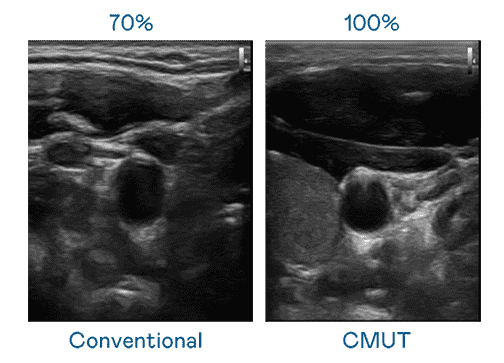

CMUT 技术是一种用电容式微机电元件来产生超音波讯号的技术。。与传统 PZT 压电式技术相比,,,CMUT 频宽增加 30%,,更宽频的超音波讯号让影像解析度大幅提升,,,是实现高影像品质医疗超音波扫描、、促进精准医疗发展的关键技术。。。。

大频宽带来超清晰影像

超音波影像的解析度高低,,首先取决于探头能发出的讯号频宽。。。。赏金国际 CMUT 可提供高清晰的超音波讯号,,,,提供高频宽、、、高灵敏度、、影像纹理细节更高的超音波影像,,,协助医护人员缩短影像判读时间及利用精准的医疗影像进行诊断。。。